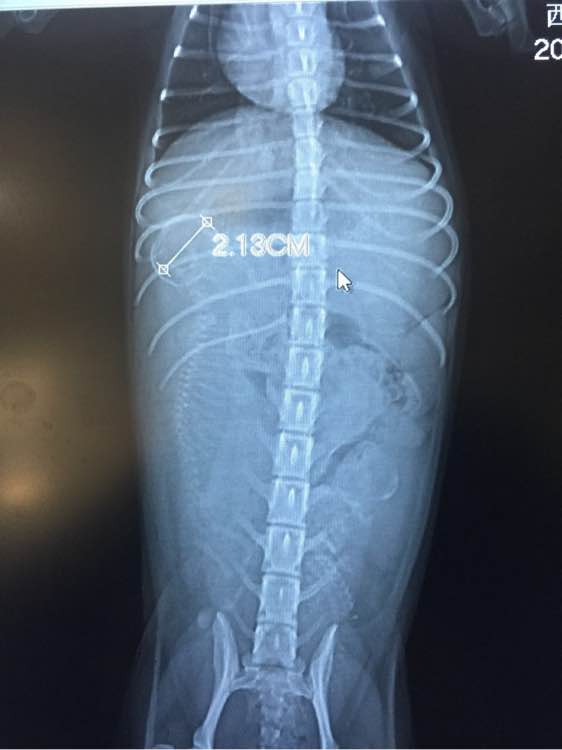

医生拍了片之后,告诉我说,小包子的说不敢再补了,小狗狗一个发育过好,一个发育不良,会影响发育不良狗宝宝的生命安全,医生嘱咐往后的日子不能给狗狗没事加鸡胸肉或者鸡蛋了!要老老实实的吃狗粮了~

刚刚医生把小狗狗的头围发给我了!我感觉是个大头宝宝,会不会难产,每天都很焦虑~